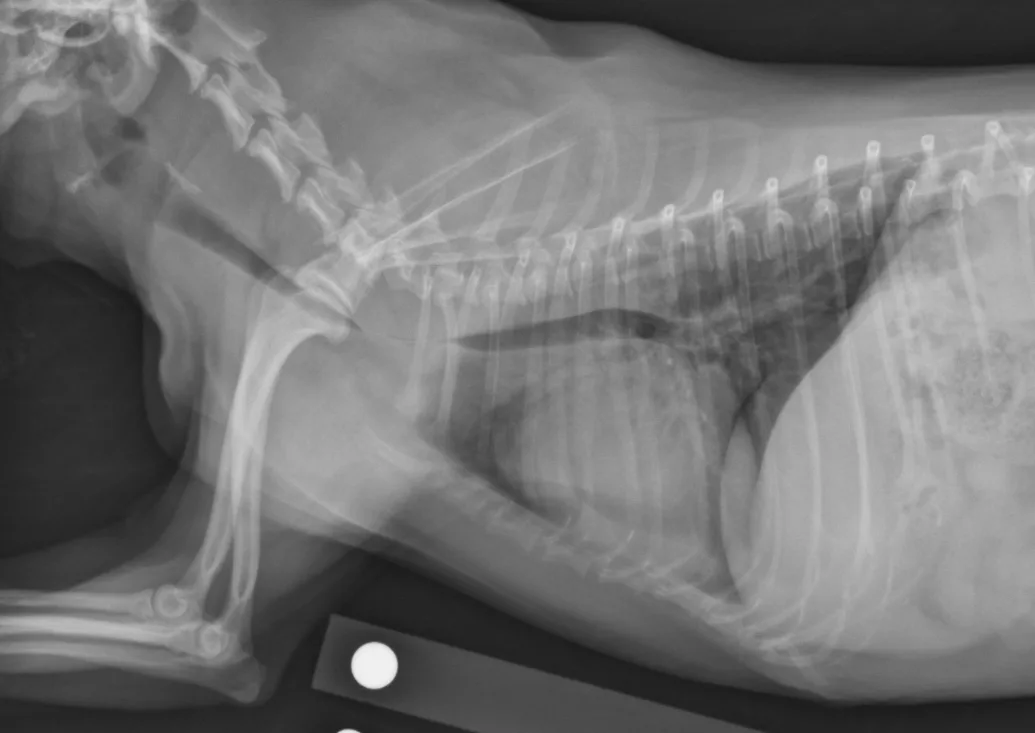

Definitive diagnosis is based on imaging (eg, survey radiography, fluoroscopy, ultrasonography, computed tomography, tracheobronchoscopy).13 Survey radiography should include dorsoventral and lateral views of the cervical region and thorax (Figure 1). Collapse of the trachea is best viewed in the cervical region during inspiration and in the intrathoracic region during exhalation.1 Radiography is critical to rule out conditions that may cause similar signs (eg, intrathoracic masses, pleural effusion) and cardiovascular abnormalities (eg, heart enlargement) that may complicate treatment. Radiography is noninvasive, cost effective, widely available, and can be performed without the risks associated with general anesthesia; however, false-positive results have been reported in 25% of dogs,14 and sensitivity ranges from 60% to 90%.2 In comparison, fluoroscopy allows direct viewing of tracheal motion during all phases of respiration, is noninvasive, and is very sensitive, although false-positive findings have also been reported with fluoroscopy.14 In one study, radiography underestimated the severity and frequency of collapse as compared with fluoroscopy.15

Lateral thoracic radiograph of a dog with tracheal collapse. The most severe area of collapse is just caudal to the thoracic inlet.